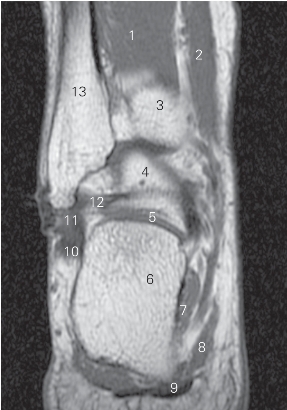

图5-43 经距腓后韧带的横断层MR T1加权图像

1

长屈肌 flexor hallucis longus 2 趾长屈肌 flexor digitorum longus

3 胫骨 tibia 4 距骨 talus

5 距下关节 subtalar joint 6 跟骨 calcaneus

7 足底方肌 quadratus plantae 8

展肌 abductor hallucis

9 趾短屈肌 flexor digitorum brevis 10 腓骨长肌 peroneus longus

11 腓骨短肌 peroneus brevis

12 距腓后韧带 posterior talofibular ligament

13 腓骨 fibula

图5-44 经远侧胫腓关节的横断层MR T1加权图像

1 胫骨 tibia 2 趾长屈肌 flexor digitorum longus

3 踝关节 ankle joint 4 胫骨后肌 tibialis posterior

5 距下关节 subtalar joint 6

长屈肌 flexor hallucis longus

7 跟骨 calcaneus 8

9 足底方肌 quadratus plantae 10 趾短屈肌 flexor digitorum brevis

11 腓骨长肌 peroneus longus 12 腓骨短肌 peroneus brevis

13 距骨 talus 14 腓骨 fibula

15 远侧胫腓关节 distal tibiofibular joint